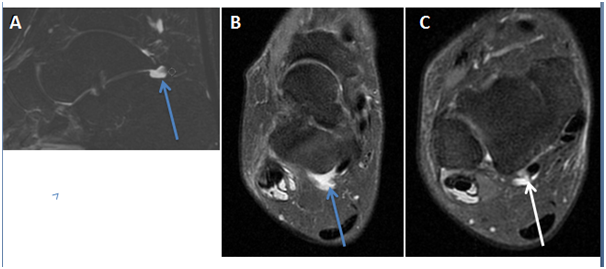

Coronal proton density MRI image of the right ankle showed a hypertrophied peroneal tubercle, it was 11.81 mm high, 5.52mm wide, and 11.20mm AP diameter. A minimal bone marrow oedema was visible in the tubercle. Both peroneal tendons were seen above the tubercle surrounded with soft tissue swelling (Figure 3).

Figure 3 (A) Coronal proton density MRI image of the right ankle shows a hypertrophic peroneal tubercle (red arrow), A minimal bone marrow oedema is seen in the tubercle. Both peroneal tendons are seen above the tubercle surrounded with soft tissue swelling (blue arrow). (B) Left side ankle for comparison shows a prominent hypertrophic peroneal tubercle (red arrow). Peroneal tendons are normal (blue arrow).

The left ankle demonstrated a prominent hypertrophic peroneal tubercle; it was 9.60 mm high, 7mm wide, and has 9.50 mm AP diameter. Peroneal tendons were seen above the peroneal tubercle, they were normal and not surrounded with soft tissue swelling (Figure 3).

Coronal fat saturated proton density MRI image of the right ankle showed both peroneal tendons located above the peroneal tubercle, they were surrounded with soft tissue swelling and high T2 signal intensity which indicates fluid effusion. Abnormal signal intensity was also seen within both peroneal tendons indicating tendonitis. The left ankle showed a prominent peroneal tubercle. Peroneal tendons were normal and intact (Figure 4).

Figure 4 (A) Coronal fat saturated proton density MRI image of the right ankle shows the hypertrophic peroneal tubercle (red arrow). Both peroneal tendons are located above the tubercle, they are surrounded with soft tissue swelling and high T2 signal intensity (blue short arrow). Abnormal signal intensity is also seen within both peroneal tendons. (B) Left ankle for comparison shows a prominent peroneal tubercle but normal peroneal tendons.

Axial fat saturated proton density MRI image of the right ankle at tibiofibular syndesmosis showed the presence of fluid within the common sheath around the peroneal tendons; it means that the fluid extension was up to the musculotendinous junction. The left side demonstrated no fluid effusion around the peroneal tendons (Figure 5 & 6).

Figure 5 (A) Axial fat saturated proton density MRI image of the right ankle at tibiofibular syndesmosis shows fluid in the common sheath around the peroneal tendons (blue arrow). (B) Left ankle for comparison shows no fluid around the peroneal tendons (blue arrow).

Sagittal fat saturated proton density MRI image of the right ankle displayed a significant amount of fluid extending down along both peroneal tendons till their bone attachments (Figure 6).

Figure 6 (A) Sagittal fat saturated proton density MRI image of the right ankle shows fluid in the common peroneal sheath and around the peroneus longus and breves tendons (blue arrows). (B) Left ankle for comparison shows no fluid around the tendons.

Sagittal and axial fat saturated proton density MRI images of the right ankle revealed fluid effusion in the right subtalar joint (Figures 7A & 7B).

Figure 7 (A) Sagittal, (B) axial fat saturated proton density MRI images of the right ankle showing fluid in the subtalar joint (blue arrow). (C) Axial fat saturated proton density MRI image at a lower level showing fluid around the flexor hallucis longus tendon (white arrow).

Axial fat saturated proton density MRI image of the right ankle confirmed the presence of fluid effusion around the flexor hallucis longus tendon (Figure 7C). Axial proton density MRI image of the right ankle proved intact muscular tendons and ligaments (Figure 8).